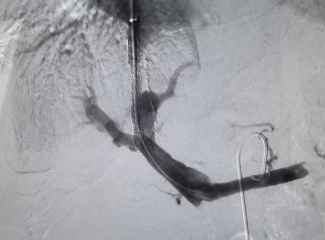

据悉,TIPS手术是在肝内开通门静脉与肝静脉之间的通道,并放置支架支撑,从而建立血管桥连接两大静脉系统通路,分流门静脉血流,达到降低门静脉高压的目的。手术通过颈部的一个小穿刺口进行,创伤小、住院时间短、患者恢复快。由于是微创手术,风险及术后并发症较传统外科手术明显降低。需要注意的是,TIPS手术是一项综合性手术,对医生能力提出了极高的要求。医生必须具备丰富的介入手术经验,也需要精通穿刺、影像识别、球囊扩张、支架植入等高精技术。

TIPS手术,是介入手术的“天花板”,需要精准的判断、精细的操作。新桥医院消化内科从2013年开展TIPS手术,TIPS技术已发展成熟。科室有徐征国教授、赵泳冰教授、周昊医师等介入专家,配备先进血管造影系统(DSA)设备,目前每年TIPS手术量超200台,经验丰富。